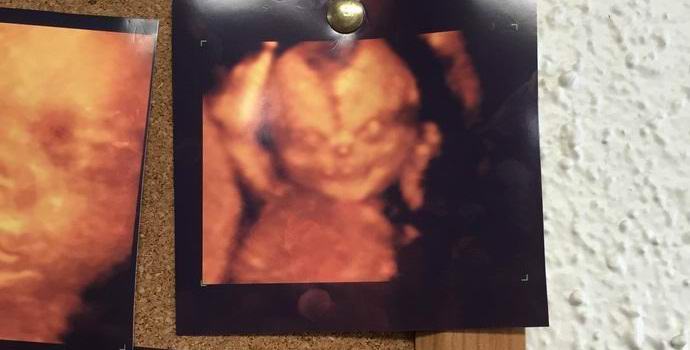

Kuva avoimet lähteet Sosiaalisen uutissivuston käyttäjät “Reddit” keskustelee aktiivisesti kuvasta saadusta sikiöstä ultraäänellä. Uutisen kirjoittajan mukaan valokuvaus roikkui lääkärin seinällä, missä hän ilmestyi hänen vaimonsa tutkia omaa jälkeläistään.

Kirjailija kirjoittaa: “Vaimoni ja minä tulimme klinikalle tekemään ultraääni tutkimuksemme lapsestamme. Kun näimme tämän kuvan, seinällä roikkuu vaimoni muutti välittömästi mieltään ultraäänitutkimuksen tekemisestä. Niin on hän pelkäsi. Lapsista oli paljon kuvia, ja niitä kaikkia olivat saman tyyppisiä, ilman pelottavia piirteitä. Kuitenkin tämä muun muassa erottuvaa kuvaa voidaan kutsua todella kauhea. Vanhempien tunteita on vaikea kuvitella joka näki tällaisen demonisen kasvot ultraäänimenettelyn aikana hänen syntymätön lapsi.

Valokuvaus aiheutti kiihkeitä keskusteluja resurssin sääntelijöiden välillä. “Mietin, onko sellaista palvelua kuin kohdunsisäinen exorcism? “- yksi käyttäjä on kiinnostunut.” Niin pieni, mutta jo absoluuttinen paha “, kirjoittaa toinen.” Katso tarkemmin hänen oikeuttaan käsi. Onko hänellä todella pullo olutta? ” kommentaattori.

Reddit-käyttäjät vertasivat kuvan merkkiä Chucky-nukkeen kuuluisasta kauhuelokuvasta ja jopa antikristuksen kanssa. Vaikka, pikemminkin yhteensä, tämä on tavallinen lapsi, joka vangittiin aikana ultraääni koko kasvoissa, mikä on muuten melko harvinainen. Tästä syystä valokuvien pelottava epätavallisuus. Voidaan vain toivoa, että tämän vauvan vanhemmat eivät ole heillä ei ole ennakkoluuloja.